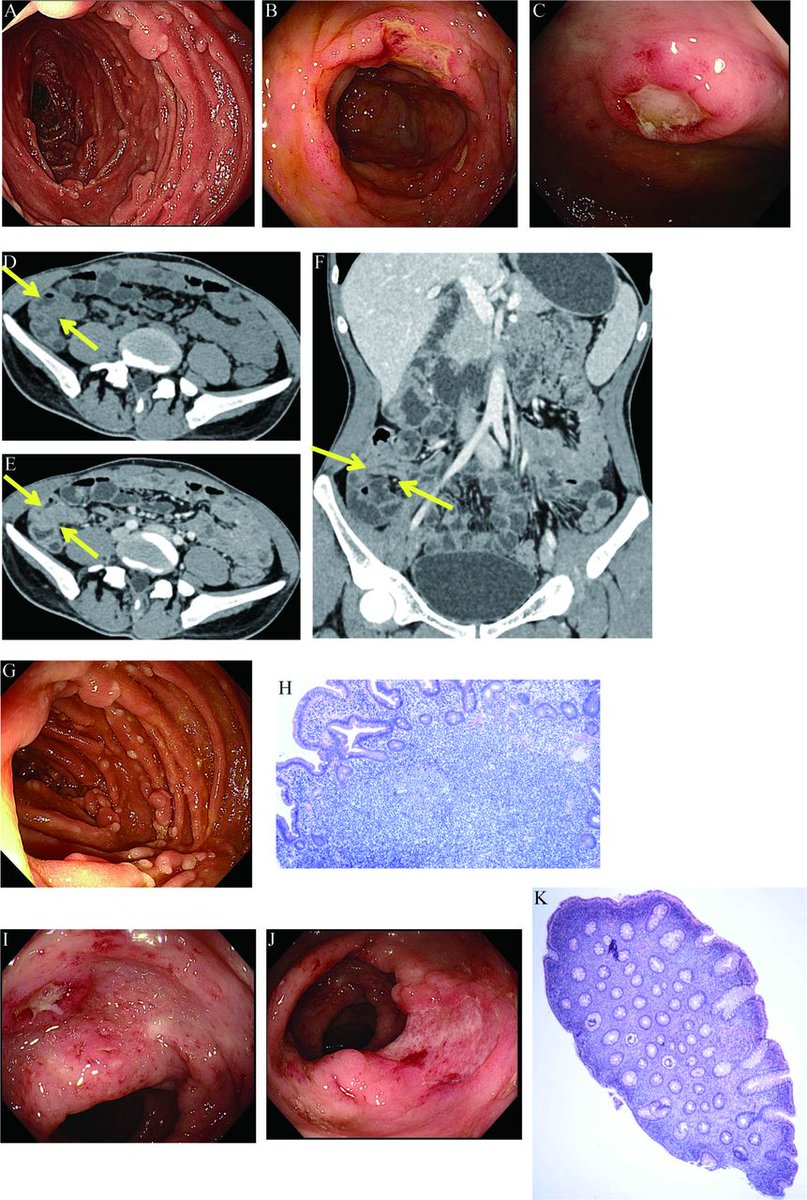

🚨 NEW in Frontline Gastroenterology! A 26-year-old man with fever, diarrhoea and haematochezia. 🔍 Endoscopy: duodenal polyps + multiple colonic ulcers 🧬 Histology: lymphoid hyperplasia and chronic active inflammation 📸 Imaging: diffuse bowel inflammation, atypical for

1

8

26